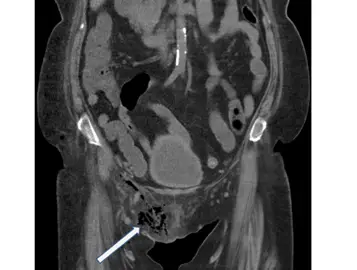

糖尿病病患主訴會陰部紅腫脹痛,血液中白血球數目增加,電腦斷層檢查呈現如圖。箭號所指之異常最可能之初診斷為下列何者?

本題核心在於辨識急性壞死性筋膜炎(necrotizing fasciitis)中最典型的局部表現——Fournier’s gangrene,即會陰部或陰囊區的壞死性筋膜炎。此疾病常見於糖尿病病患,臨床上以局部紅腫、腫脹、劇痛及全身感染表徵(發燒、白血球上升)為主。影像學上,CT 最關鍵的是確認皮下或筋膜層次的空氣存在(subcutaneous emphysema)與筋膜增厚、組織水腫等表現。

提供之電腦斷層(CT)冠狀面影像可見:

- 會陰部皮下組織廣泛散在的低密度條狀或斑塊(箭頭所指),與空氣相符,呈現「髒」的汙染性氣體陰影。

- 周邊軟組織可見模糊筋膜增厚與脂肪紋理增生,反映嚴重炎性滲出與壞死。

- 未見明顯腸管或網膜突出於腹股溝或閉孔區,排除各類腹股溝、股動脈及閉孔疝氣表現。

以上「皮下空氣」為本案例影像診斷的關鍵,最符合壞死性筋膜炎中常見的皮下氣腫表徵。